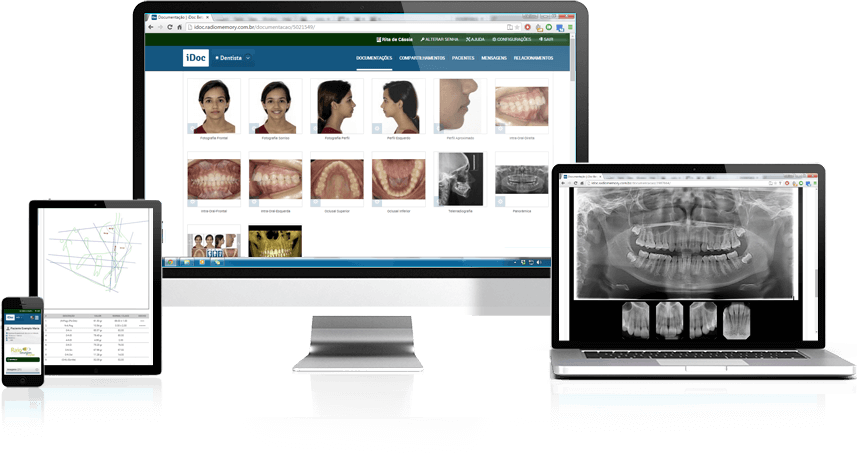

DOCUMENTAÇÃO ORTODÔNTICA

A documentação ortodôntica é um conjunto de exames (radiografias, fotografias intra e extrabucais, análises cefalométricas e de modelos 3D) que proporciona uma visão abrangente do paciente, permitindo maior detalhamento no exame do caso inicial.

Sem a documentação ortodôntica , o ortodontista não consegue realizar diagnóstico apurado das anomalias do paciente que deseja se submeter ao tratamento ortodôntico ficando, portanto no escuro para tomada das decisões.

Além de favorecer o tratamento, a documentação ortodôntica é uma excelente ferramenta de acompanhamento, demonstrando os avanços estéticos do paciente.